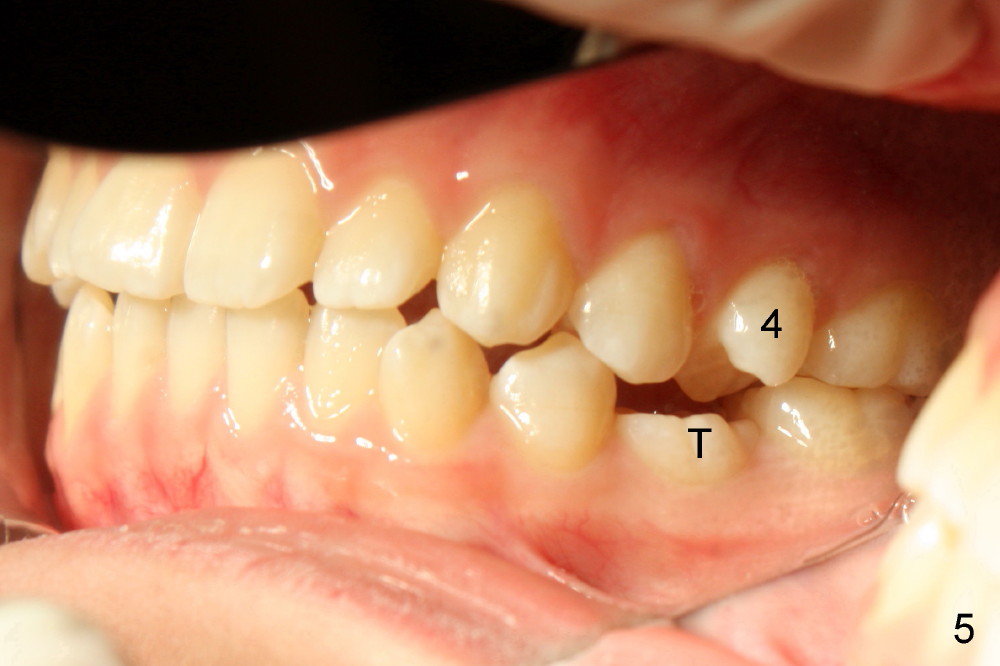

A 13-year-old Asian girl seeks orthodontic treatment for crowding. The lower 2nd bicuspids are congenitally missing (Fig.1,8), whereas the upper right one rotates 180° and the upper left is partially impacted (Fig. 1, 7). The lip muscles strain when the lips close (Fig.3). Orthodontic treatment started with extraction of four affected teeth (#4,13, K and T) 6 months ago. .018' niti wires are being used. Dental midlines do not coincide preop and intraop (Fig.4,4'). Pre-op front view shows that the upper dental midline coincides with the facial one (Fig.1'). There is Class I canine and molar relationship on the right (Fig.5,5',9,9'); open bite on the left (Fig.6,6',10,10').